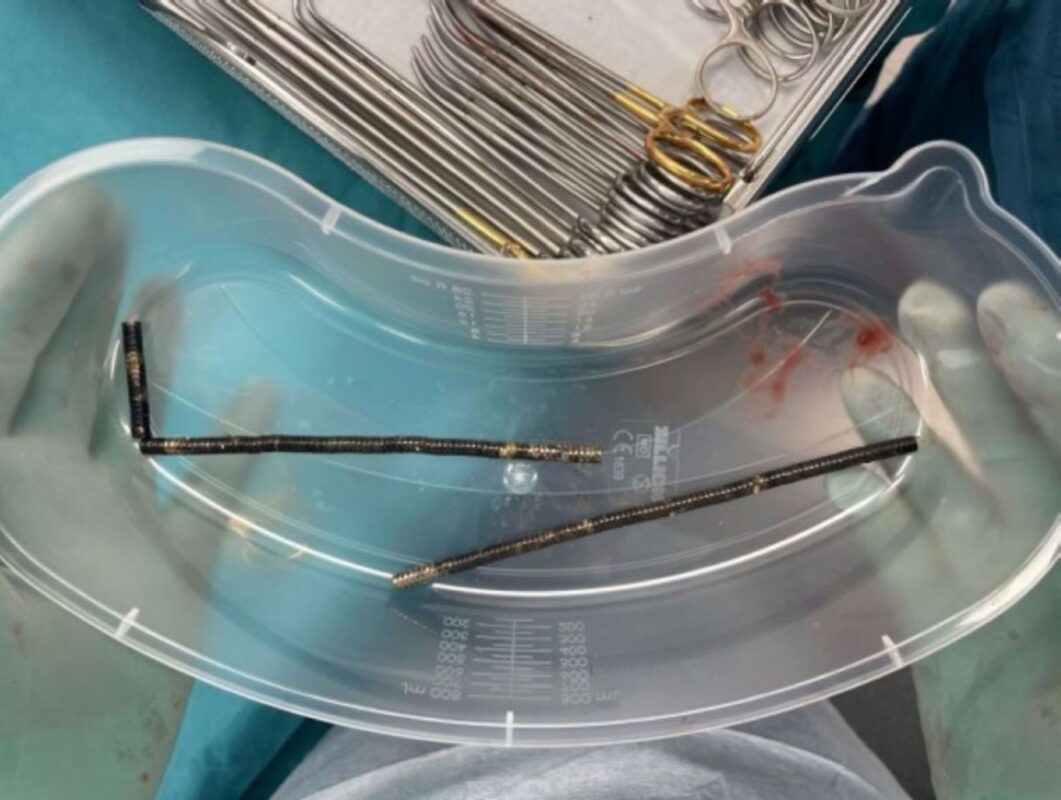

Os exames mostraram que os ímãs haviam se agrupado em quatro correntes dentro do abdômen, unindo diferentes partes do intestino. A forte atração magnética fez com que o órgão sofresse necrose por pressão, quando o tecido morre por compressão prolongada, o que exigiu uma cirurgia imediata.

Durante o procedimento, os cirurgiões conseguiram remover os ímãs, mas parte do intestino delgado e grosso precisou ser retirada. O adolescente permaneceu hospitalizado por oito dias até receber alta.